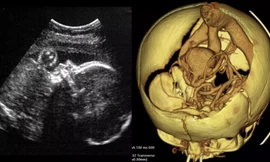

TPO - Ngày 28/5, một dấu mốc y khoa đặc biệt đã được ghi nhận tại TP.HCM khi các bác sĩ Bệnh viện Từ Dũ và Bệnh viện Nhi đồng 1 phối hợp thực hiện thành công ca can thiệp tim bào thai thứ 9 – ca bệnh cực kỳ phức tạp cho một thai phụ quốc tịch Singapore. Trước kỳ tích này, Bộ trưởng Bộ Y tế đã gửi thư khen, biểu dương tinh thần vượt khó, trình độ chuyên môn và y đức cao cả của đội ngũ thầy thuốc Việt Nam.

TPO - Dị tật tim bẩm sinh hiếm gặp – không lỗ van động mạch chủ - có tỷ lệ tử vong rất cao nếu không được can thiệp kịp thời. Bệnh viện Singapore đã chủ động giới thiệu sản phụ sang điều trị tại Bệnh viện Từ Dũ và Nhi Đồng 1 TPHCM.

TPO - Liên tiếp 2 ca thông tim xuyên tử cung, cứu sống thai nhi bị dị tật tim nặng ngay khi còn trong bụng mẹ đã được Bệnh viện Từ Dũ phối hợp cùng Bệnh viện Nhi Đồng 1 thực hiện thành công. Kỹ thuật này vừa được trao giải thưởng Thành tựu Y khoa Việt Nam tối 26/2.

TPO - Ngày 30/1, Bệnh viện Từ Dũ TPHCM cho biết, cháu bé được thực hiện thành công ca thông tim xuyên tử cung đầu tiên tại Việt Nam đã chào đời khỏe mạnh với cân nặng 2,9kg.